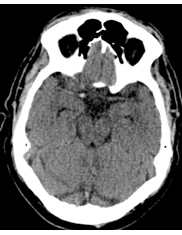

The patient undergoes a repeat non-contrasted CT brain scan (Figure 5).

Figure 5. Results of the repeat non-contrasted CT brain scan image.

Based on the non-contrasted CT brain scan image and after patient was treated with IV nicardipine to lower her current BP of 140/72 mm Hg, what is the best next step in management?

Based on the repeat CT brain scan showing acute right frontotemporal intracerebral hemorrhage and concern for post-IV thrombolytic symptomatic hemorrhage, the best next step would be to administer IV thrombolytic reversal agents. This is often done after obtaining a complete blood count, prothrombin time, aPTT, fibrinogen level, and type and cross-match followed by administration of combined cryoprecipitate and tranexamic acid or aminocaproic acid.